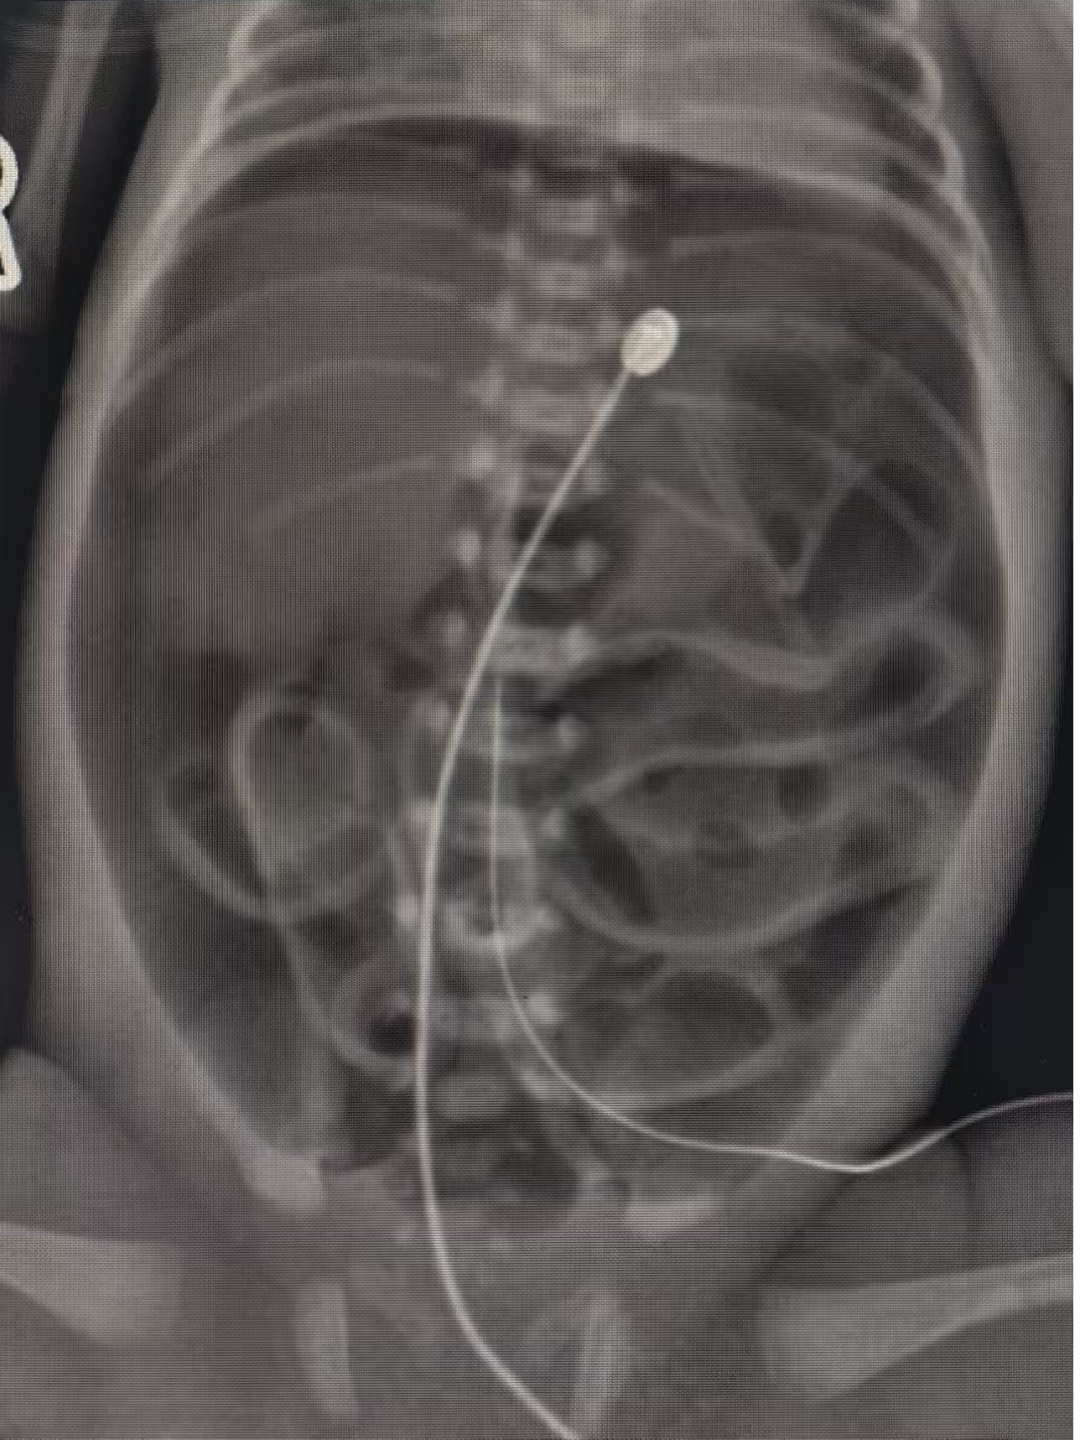

时间就是生命!医护人员立即启动紧急处置流程,床旁X光检查结果显示腹腔内存在大量游离气体,提示消化道穿孔可能。新生儿科第一时间联系小儿外科紧急会诊,小儿外科执行主任聂梅兰带领团队火速赶赴NICU,结合患儿临床表现、影像学检查结果,精准研判为胃破裂。

手术台上,聂梅兰带领团队凝神聚气、精准操作。由于患儿体型极小,腹腔空间狭窄,手术视野受限,每一次操作都需极致精细。团队小心翼翼打开腹腔,探查发现胃大弯上方有一处约4厘米的破裂口,随即有条不紊地逐层精细修补胃壁破口,同时用温盐水仔细冲洗腹腔,最大限度降低感染风险。手术室护士长张岚带领护理团队默契配合,精准传递器械,为手术顺利推进提供坚实保障。经过多学科团队的奋战,手术圆满成功,患儿生命体征趋于平稳,被安全送回NICU接受后续高级生命支持。